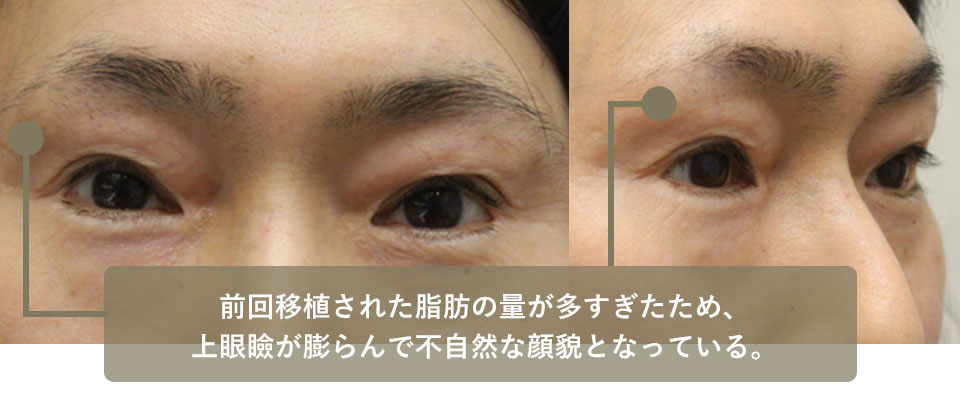

After undergoing surgery for a droopy eyelid at the Plastic Surgery Department of E University Hospital, he became concerned about the concavity of his upper eyelid.

After undergoing two surgeries at F Cosmetic Surgery in Tokyo to transplant fat from the groin into the upper eyelid, he came to our hospital for excision because his eyelid had bulged out this time. The previous transplanted fat protruded forward and gave her an unnatural look.

After excision of a small amount of skin and transplanted fat, a beautiful and natural looking eyelid was achieved.

| Before surgery | The amount of fat transplanted last time was too large, resulting in a bulging upper eyelid and unnatural facial appearance. |

|---|---|

| After surgery | Excision of skin and grafted fat, followed by creation of a double eyelid. The result was natural, although a slight depression was noticeable. |

| Before surgery | The amount of transplanted fat was too large, causing the upper eyelids (especially the inner ones) to bulge, resulting in an unnatural facial appearance. |

|---|---|

| After surgery | Excision of skin and grafted fat, followed by creation of a double eyelid. The result was natural, although a slight depression was noticeable. |